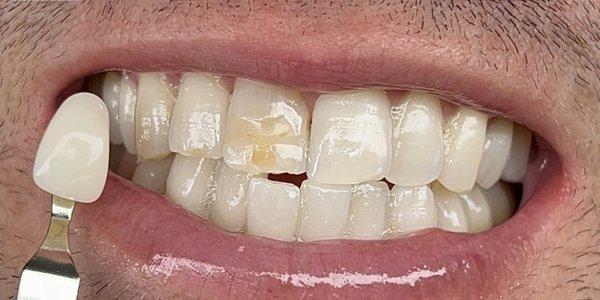

ManeTained is a hair salon in Costa Mesa, CA that offers a range of hair services for both men and women.

With a team of skilled stylists, ManeTained provides haircuts, coloring, and styling services to help clients achieve their desired look.